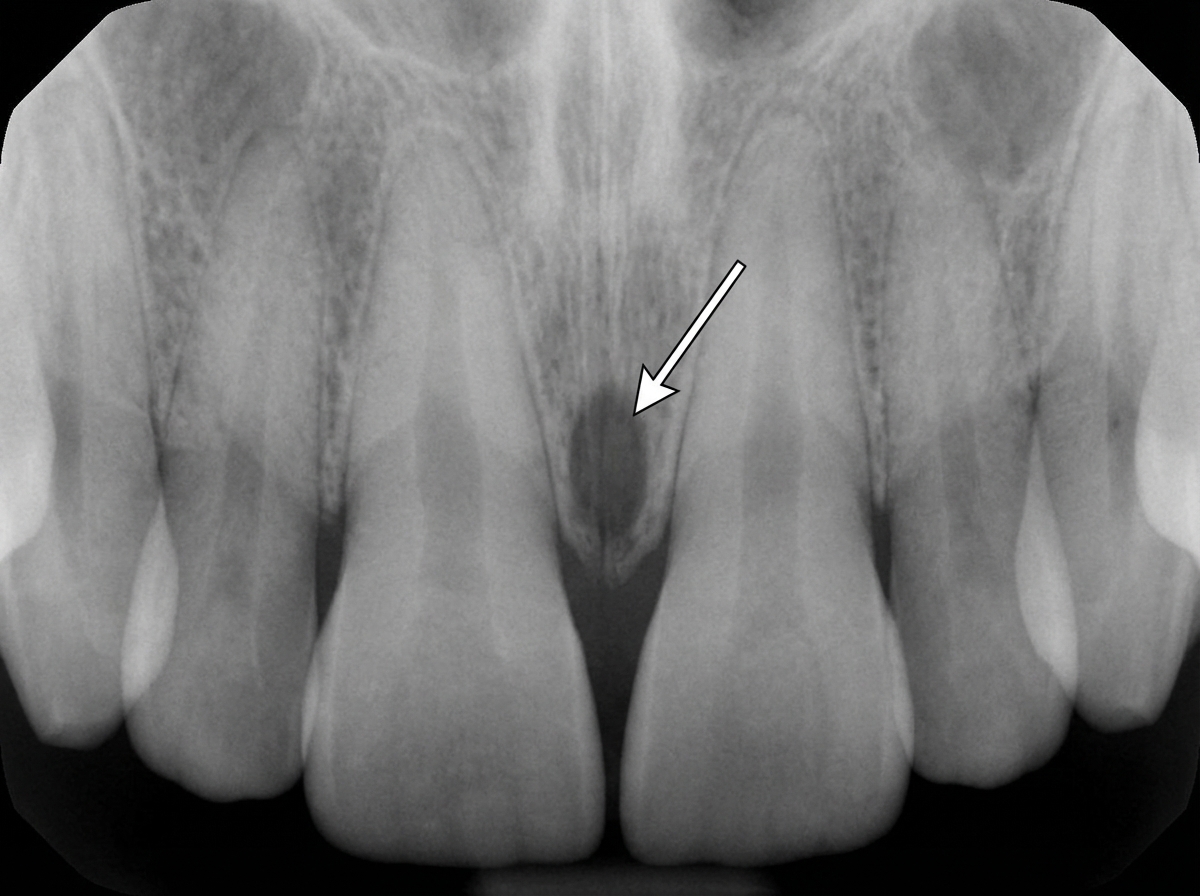

The structure marked with arrows is:

Explanation: ***Incisive foramen*** - Appears as a **midline radiolucency** between the maxillary central incisors on periapical or occlusal radiographs - Represents the **opening** of the incisive canal at the oral surface of the hard palate, allowing passage of **nasopalatine vessels and nerves** *Empty trabeculae* - Refers to **trabecular bone spaces** that appear as small radiolucencies throughout bone tissue - These are **scattered** throughout the maxilla and mandible, not localized as a single midline structure *Incisive canal* - Represents the **entire bony canal** extending from the nasal floor to the oral cavity - Appears as a **vertical radiolucent line** on lateral views, not the circular opening seen in this case *Midline suture* - Appears as a **thin vertical radiolucent line** between the maxillary bones - Extends **superiorly** from the alveolar crest, different from the rounded foramen appearance